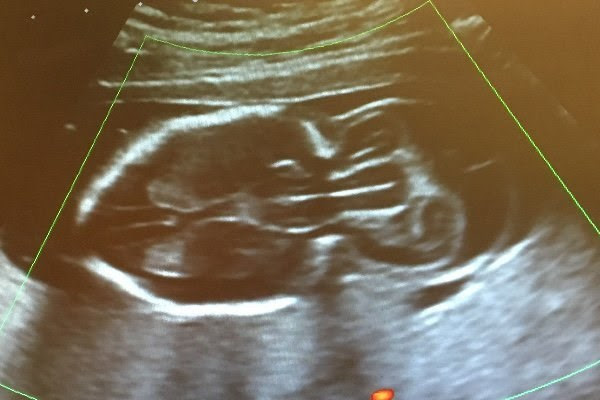

ảnh minh họa

Khám thai lúc 20 tuần thì bác sĩ đã phát hiện ra điều này khiến giấc mơ của Analee bị vỡ vụn. Cô chẳng còn thiết tha làm những việc mà bà mẹ mang thai lần đầu nào cũng hứng thú như mua nôi, xe đẩy, quần áo trẻ sơ sinh.